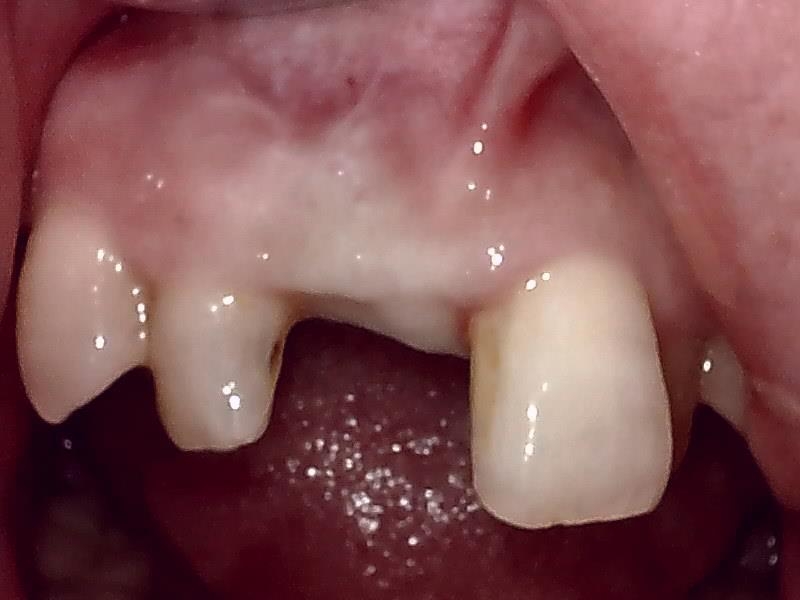

GBR骨造成後の10ヶ月経過した健全な顎堤の状態です。

抜糸後、2週間経過した歯肉の状態です。

歯肉の整形 とても綺麗な良い歯肉の状態です。